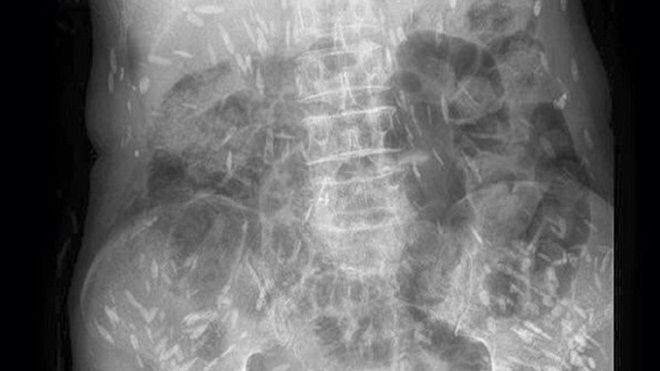

Trong những ngày qua, trên mạng xã hội chia sẻ rất rầm rộ về một hình ảnh chụp Xquang, kèm theo hình ảnh này là lời cảnh báo: “Hình ảnh được ghi nhận tại Bệnh viện đa khoa Trung ương Thái Nguyên.

Người gạo là có thật các bác ạ. Hình ảnh XQ trên là của bệnh nhân nhiễm sán xơ mít do ăn phải thức ăn sống (có thể là rau sống, tiết canh, gỏi cá…) có nhiễm trứng, ấu trùng sán…”.

Rất nhiều người khi quan sát hình ảnh này không khỏi hốt hoảng khi hình những nốt trắng được cho là sán sơ mít có ở khắp cơ thể. Thậm chí, có người còn bình luận: “Người nhiều sán thế này, có khi đứt tay máu không chảy mà sán lại chạy ra”.

Để có thông tin rõ hơn về mặt chuyên môn, chúng tôi đã chuyển hình ảnh này đến BS Trần Huy Thọ - Trưởng khoa Điều trị (Viện Sốt rét - Ký sinh trùng - Côn trùng Trung ương), thì được biết, viện cũng đã gặp nhiều trường hợp bị sán cơ, tuy nhiên nhìn hình ảnh như trên phim thì bản thân bác sĩ Thọ chưa gặp bao giờ.

“Nhiều khả năng đây là sán cơ, tuy nhiên để khẳng định chính xác thì tôi phải hỏi bệnh sử, có hồ sơ bệnh án, kết quả làm các xét nghiệm, thậm chí là cả địa phương nơi đó tập quán ăn uống như thế nào, nếu chỉ nhìn vào hình ảnh thì không thể khẳng định 100%”, BS Thọ cho hay.

Theo bác sĩ Thọ, trong trường hợp sán cơ nhiều như vậy, thì đó có thể là những nốt vôi hóa ở trong cơ. “Đây có thể là những nốt vôi hoá trong cơ, khi nang sán trong cơ thoái triển và thành vôi hoá”, BS Thọ cho biết.